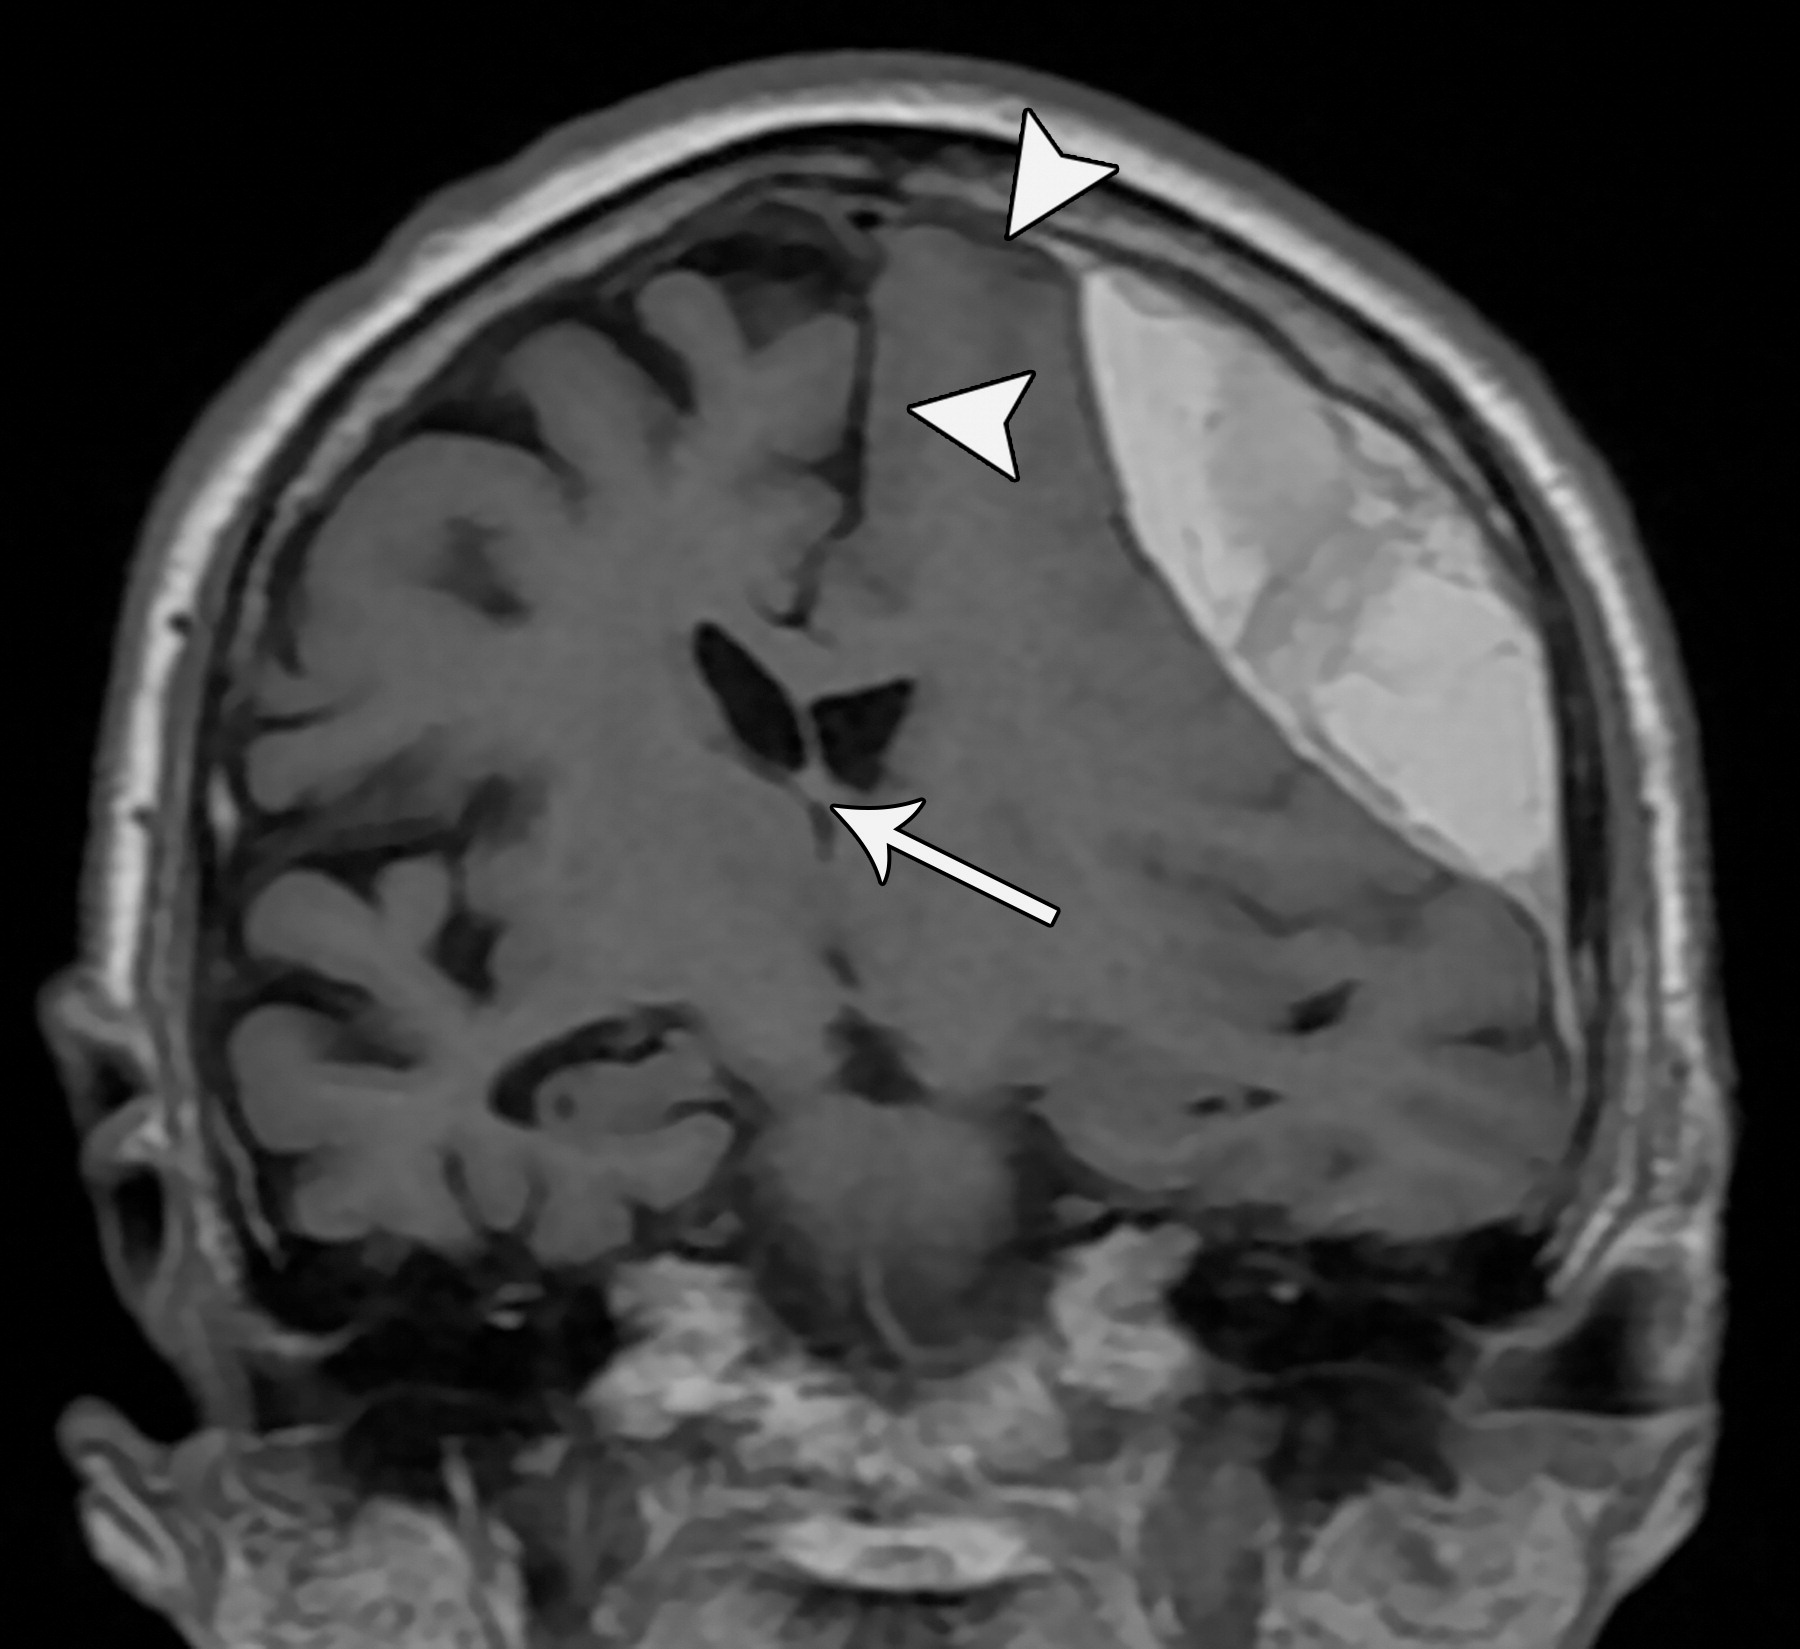

e10b81f69aecfde7ed5f5612478dbcdc.jpeg

33岁男性,生殖细胞肿瘤脑转移患者的大脑镰下疝:冠状增强CT示大脑穹隆游离缘下方的扣带回从左向右疝入(白色弯箭头),并伴同侧胼胝体(*)的下侧移位,注意同侧脑室受压和对侧脑室的扩张(白色箭头)。

b970e936c5e18c5c1ffcf84ad6aaa810.jpeg

分房性硬膜下血肿及大脑镰下疝。左侧额叶挤压大脑镰(白色短箭头),以及蛛网膜下腔的消失。同时需要注意室间孔略向右侧移位(白色长箭头)。